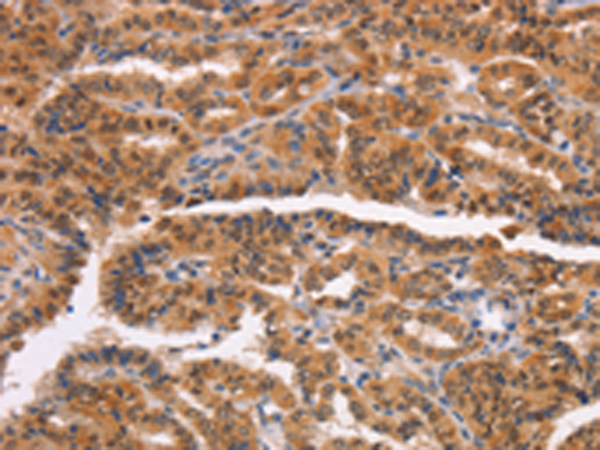

分类: 科研抗体货号: P11601别名: GTB; NAGAT; A3GALNT; A3GALT1应用: IHC反应种属: Human